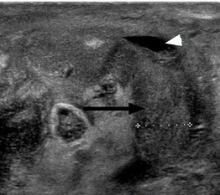

Hydrocele

- Anechoic fluid adjacent to the testicle